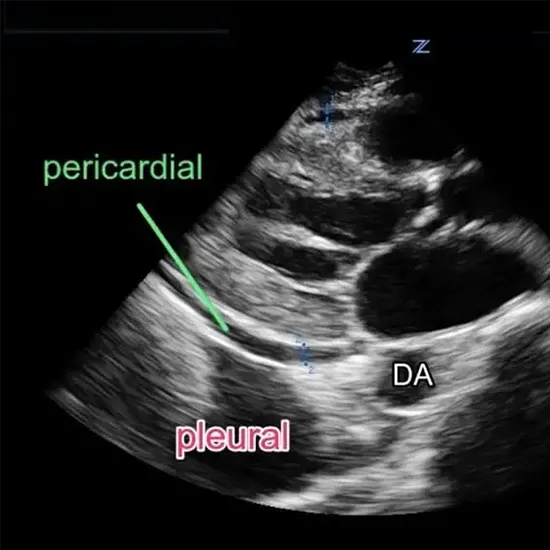

The Ultrasonography (USG) test for pericardial effusion is an imaging test in which ultrasound is used to make an image of the heart and the pericardial space. The pericardial space is the region between the two layers of the heart's membrane covering the pericardium.

For assessing pericardial effusion, with or without tamponade, echocardiography—a type of ultrasound examination of the heart—is the gold standard. A dilated inferior vena cava, right atrial collapse, right ventricular diastolic collapse, and inspiratory valvular abnormalities are among the specific findings.

When utilising time-motion (T/M) or real-time ultrasound technology to examine the heart through a left chest intercostal gap, pericardial effusions are typically found.